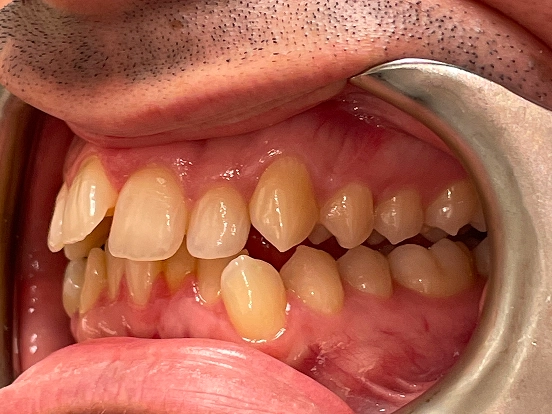

Invisalign DT

DT’s transformation with Invisalign is a perfect example of how advanced orthodontic technology can deliver incredible results. The clear aligners gradually corrected the alignment and bite issues, creating a straighter, healthier, and more attractive smile—all without noticeable brackets or wires.